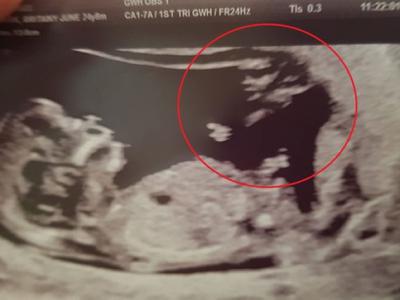

英国不易受孕年轻夫妻奇迹怀孕 超音波照

英国不易受孕年轻夫妻奇迹怀孕 超音波照惊见“天使”守护神(蜘蛛网eeook.com报道)...